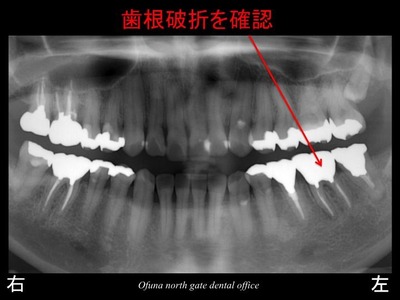

診査の結果、歯根破折 と診断されました。

先週の症例も歯根破折 でしたが、本当によくあることなのです。

神経のない歯についてはこのブログでもよく紹介してきました。

神経のない歯は もろく 通常の咬む力でも割れてしまうことがあります。

こうした状態を患者さんに説明する時に ” 木 ” に例えてお話しすることがあります。

生き生きとした木はたたいたり、

蹴ったりしても折れたりすることはありませんが、

枯れた木は折れる可能性があります。

神経を取った歯も枯れた木と同じような状態になります。

神経のない歯は血液供給がなくなるため 脆く(もろく)なってしまうのです。

先ほどの症例と同様に歯根破折 していました。